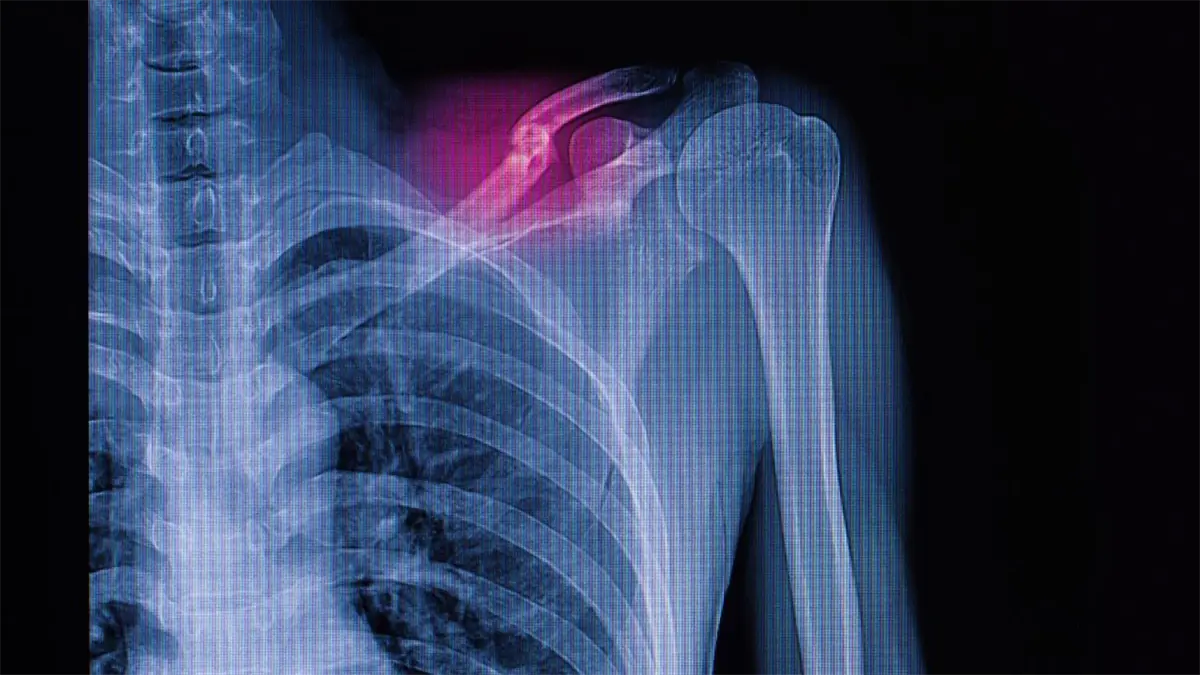

Fractura en el hombro